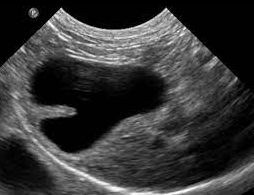

고양이 2중 담낭에 대한 분류

그런 노력의 한 가닥이 이 논문이다.

나중에 분류적으로 특정 질환의 손인과 연관이 밝혀진다면 큰 의미를 갖겠지만 그때까지는 그저 이런게 있군 하는 수준으로 받아들이길.